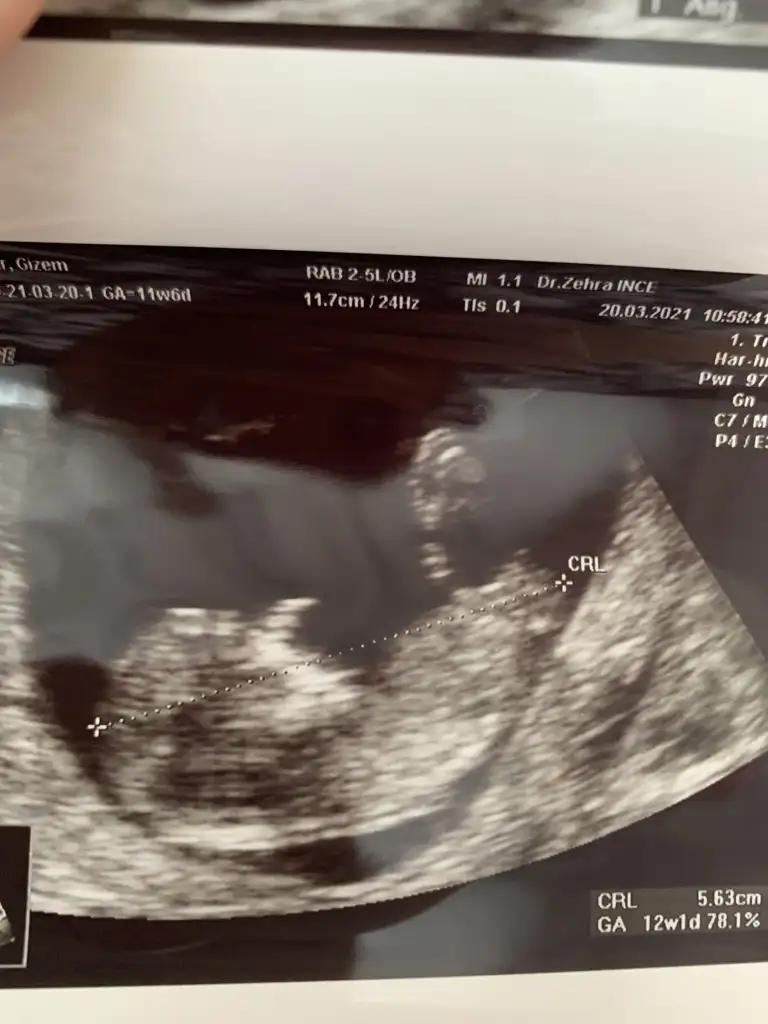

12+3 haftalik benim bebegimide yorumlar misin?Ikra meyra

Alttaki bacak arasi görüntüsü

doktorum 1 ay sonra söylerim dedi merak ediyorum.. :)

videodan ss aldim